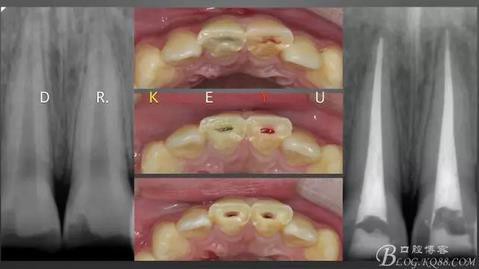

CASE 4—18歲少年,冠折后半年來診

360截圖20170120135125763.jpg

0、根管治療(千里之行始于根下)